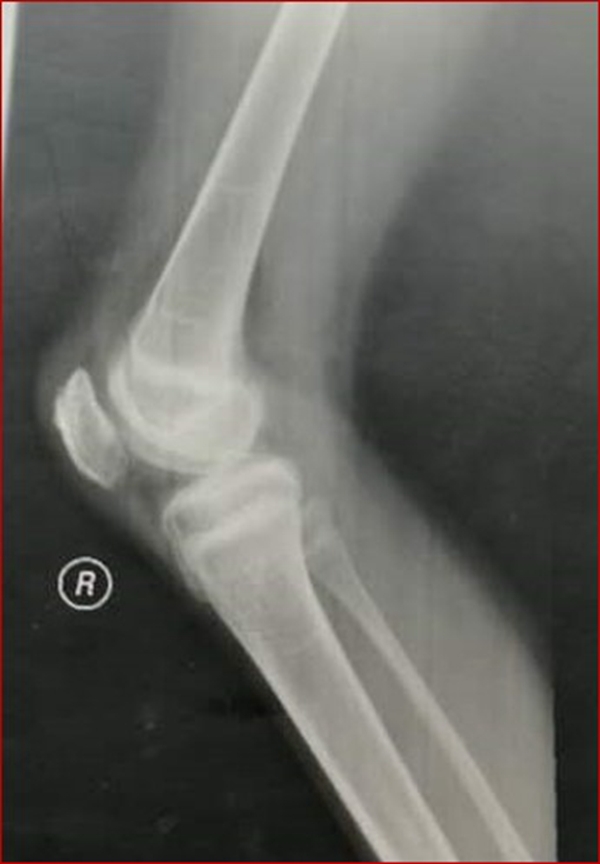

图2 受伤3周X线片

考虑此患儿伤后已3周,组织全科讨论,确定诊断为:髌骨上极陈旧性套状撕脱骨折。充分与家属沟通远期预后。